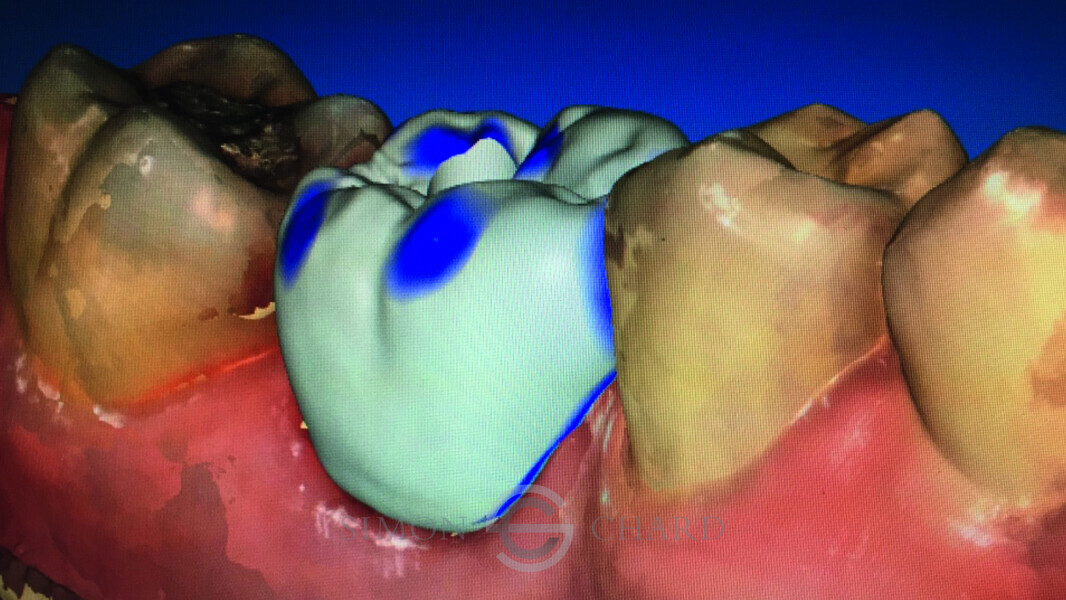

Implant restoration with CEREC